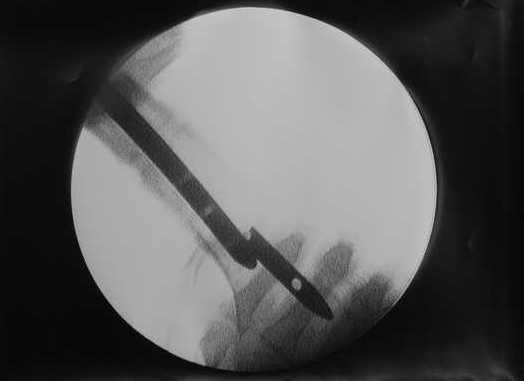

> Очень было бы любопытно посмотреть поэтапные Р-снимки с ЭОПа (хотя

В приложении пример, как их использовали после остеотомии бедра по поводу сросшегося с вальгусом перелома, чтобы не дать гвоздю уйти во внутренний мыщелок.

Да, действительно красивый клинический пример: виден вальгус до операции и последующая коррекция углового смещения на "полярах". Я так понимаю, что в вашей клинике есть возможность использовать различные фиксаторы. Почему не использовали DFN? Спицы какие используете? Киршнера или Илизаровские? С виду очень тонкие...